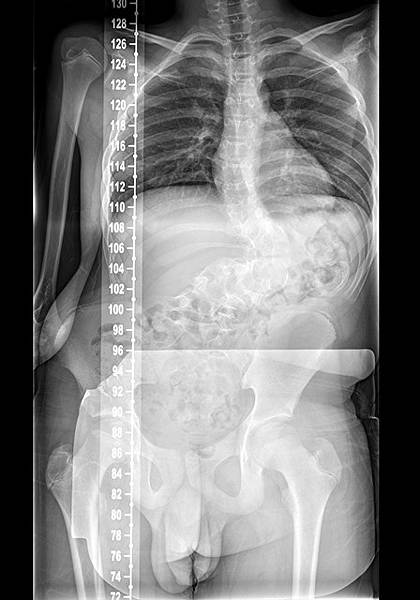

【柿子日報記者李玲/台南報導】12歲的陳小弟因先天性半椎體發育異常,導致嚴重脊椎側彎,4年前至成大醫院脊椎外科就診並追蹤觀察。疫情期間未持續就診的陳小弟,今年回診時,脊椎側彎角度已明顯惡化,角度超過100度,必須進行手術。脊椎畸形矯正手術難度極高,風險包含大出血及脊椎神經損傷,嚴重者可能導致癱瘓甚至死亡。經過15小時的手術,由成大醫院脊椎外科主任林政立醫師、台北慈濟醫院脊椎畸形矯正專家曾效祖醫師、成大醫院骨科部劉原輔醫師和神經外科李柏萱醫師協力合作,於智能複合式手術室成功完成艱難的矯正手術。術後陳小弟恢復狀況良好,能夠正常進行日常生活,家屬也對手術成果相當滿意。

成大醫院脊椎外科主任林政立醫師表示,脊椎側彎好發於青少年時期,校園健康檢查有機會能早期發現,透過背架矯正及定期追蹤,降低開刀必要性。然而,當脊椎側彎角度大於40度時,背架矯正效果有限,肩膀、骨盆或背部會出現不對稱,嚴重者可能影響呼吸及消化功能,需透過手術來矯正。